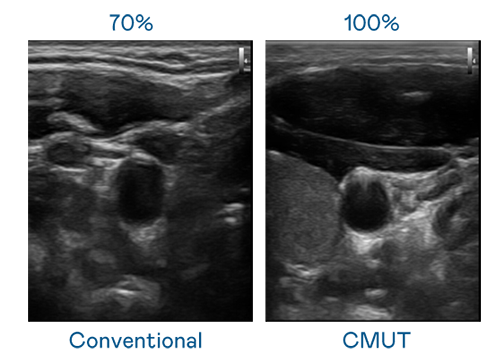

CMUT 技術是一種用電容式微機電元件來產生超音波訊號的技術。與傳統 PZT 壓電式技術相比,CMUT 頻寬增加 30%,更寬頻的超音波訊號讓影像解析度大幅提升,是實現高影像品質醫療超音波掃描、促進精準醫療發展的關鍵技術。

超音波影像的解析度高低,首先取決於探頭能發出的訊號頻寬。BBIN宝盈 CMUT 可提供高清晰的超音波訊號,提供高頻寬、高靈敏度、影像紋理細節更高的超音波影像,協助醫護人員縮短影像判讀時間及利用精準的醫療影像進行診斷。